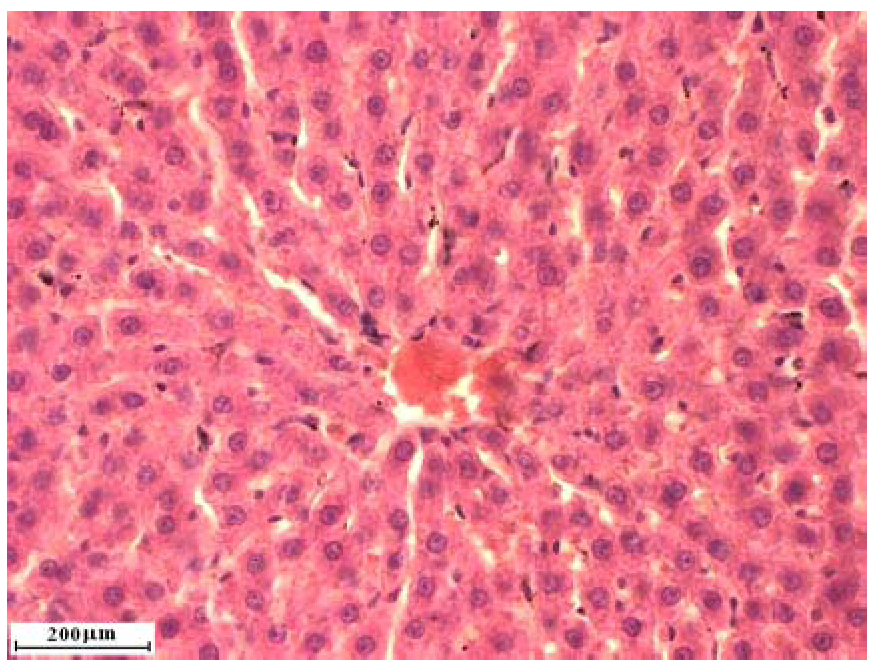

2.2. Liver cross sections